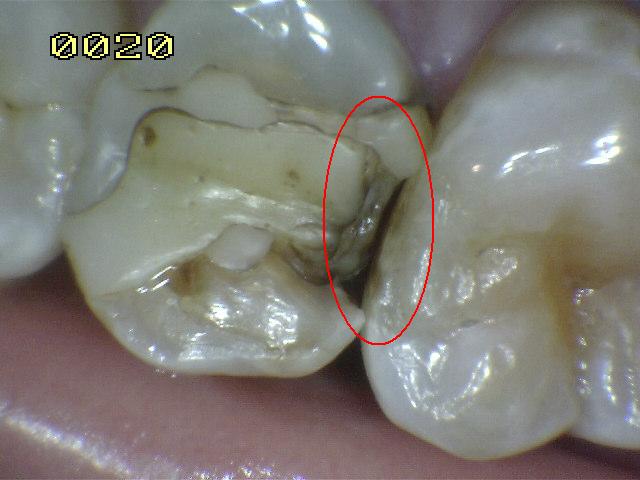

Código 5

(Caries Severa): Cavidad

detectable con dentina visible hasta la mitad de la superficie

-

Cavidad detectable

adyacente a la restauración/sellante con dentina visible

en el espacio de interfase con signos de caries tal como

se describe en el código 4, además de un espacio > 0,5

mm de ancho.

En los casos en que

los márgenes no son visibles, hay evidencia de pérdida

de continuidad en el margen de la restauración/sellante

y en la dentina, detectada por el paso de la punta de

0,5 mm de la sonda cuando se pasa por el margen de la

restauración/sellante.

Criterios para

determinar si la lesión es activa o detenida